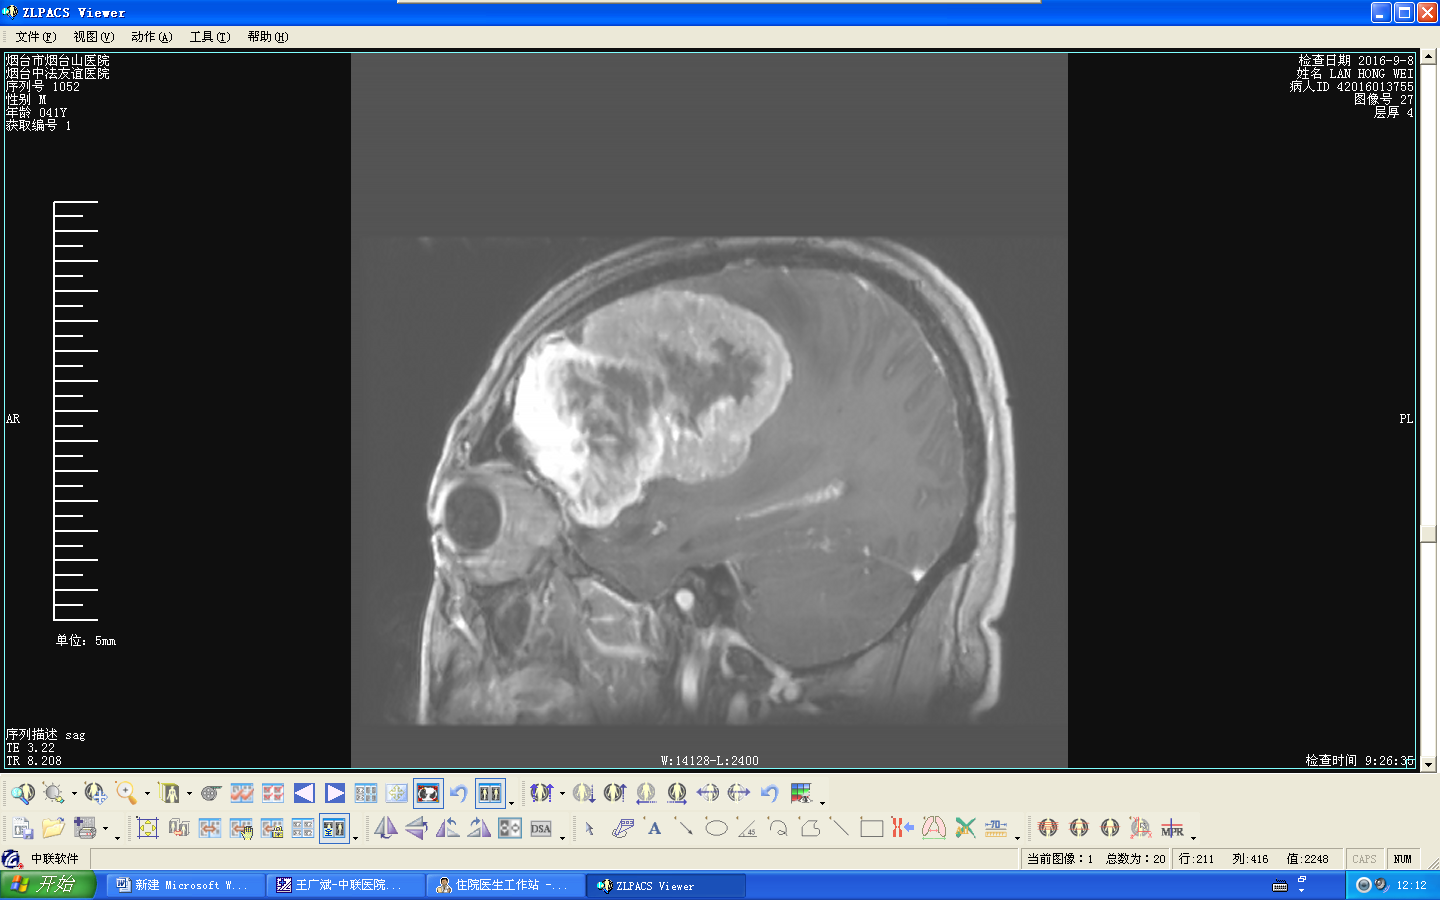

(大团灰白相间物即为肿瘤,约三分之一的颅腔已被肿瘤“侵占”)

患者10个月前无明显诱因始感头痛头晕,并渐出现言语含糊不清,右侧肢体活动不灵,思维紊乱、情绪激动易怒等。当地医院行颅脑CT检查示脑内巨大肿瘤。曾到多家大医院进行诊治,均因肿瘤巨大、脑组织受压严重,与周围大血管粘连紧密,手术难度大且可能大出血死亡等,均建议病人到北京、上海等大医院的神经外科手术。由于病人家庭特别困难,不能到大医院就诊。绝望的家属带患者来到我院,经过系统检查,确诊为罕见的脑内巨大脑膜瘤,肿瘤位于左侧额叶,基底在前额及眶上壁,约10.3cm×7.8cm×7.5cm大小,向后压迫左侧中央运动中枢、感觉中枢、语言中枢等重要功能区,中线侵犯大脑镰并向右脑移位达2cm,与大脑前动脉、大脑中动脉、前交通动脉、前矢状窦等主要大血管包绕紧密。肿瘤巨大,脑受压严重,随时有发生脑疝、引起严重不良后果的可能。经神经外科刘建辉主任组成以胡佳副主任医师、医学博士为主的神经外科治疗团队,对病人进行完善的术前准备,与全科一起仔细分析讨论,制定了详尽的手术方案。并与麻醉科、手术室、重症监护室等相关科室共同讨论术中配合,可能发生的意外及处理方法、术后治疗护理方案。9月18日,经神经外科、麻醉科、手术室共同努力成功切除肿瘤,整个手术历时11个多小时,术中失血仅800ml。